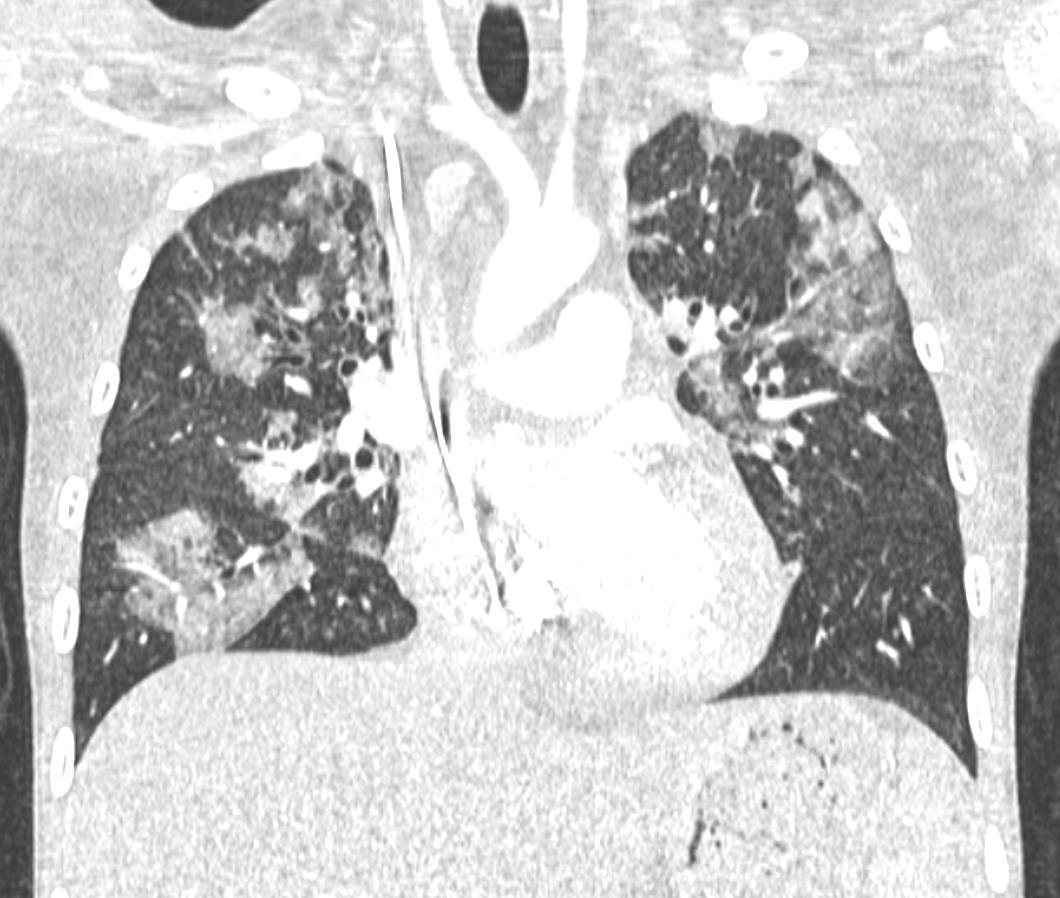

Acute Pediatric COVID-19: CT

21 Imaging of Covid 19 infection in children

3 Phases

Progressive: Diffuse GGO

Developed: Consolidation

• Patchy bilateral GGO, Consolidations or both

• Peripheral and lower lung zone predominance

• Bilateral & multifocal GGO, +/Consolidations or both

• Halo sign

• Peripheral and subpleural

• Bronchovascular thickening

COVID 19

• Halo sign (Early)